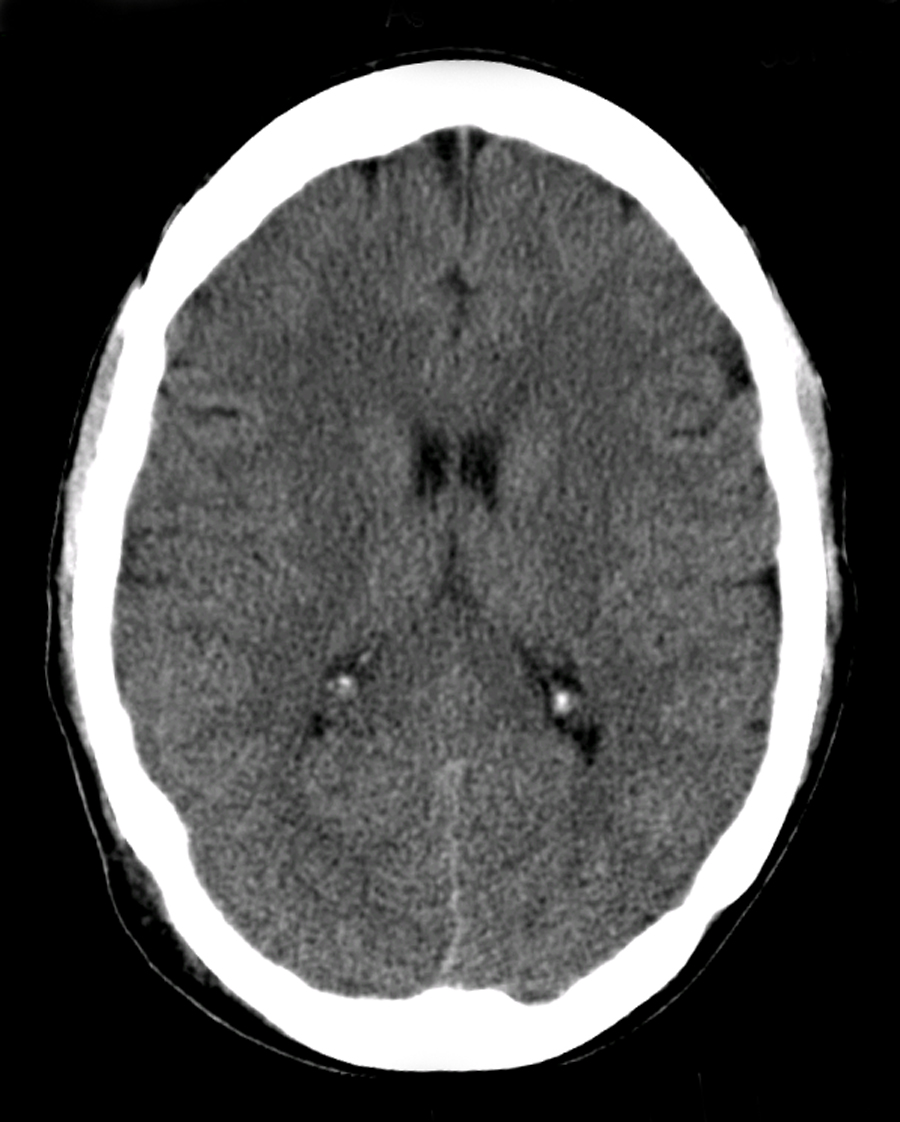

Now that we know how to systematically go through a Head CT scan, let’s have a look at how we would interpret the CT we saw at the beginning.

CT Head Interpretation

D – This is a CT Head taken on ….., of the following patient….. Is there a previous CT scan to compare to?

On initial inspection, there is no obvious pathology, but I will proceed to go through it systematically.

B – Looking at the film, there are no signs of an extra/subdural bleed and no intracranial bleeding.

C – The cisterns are clear and no sing of a subarachnoid haemorrhage.

B – The are no signs of a midline shift. There is no area of hypo/hyperdensity and no obvious masses or ring-enhancing lesions.

V – The ventricles are not enlarged and there is no signs of an intraventricular bleed. There is some calcification of the choroid plexuses

B – There are no obvious skull fractures.

In summary this is a normal CT-Head.